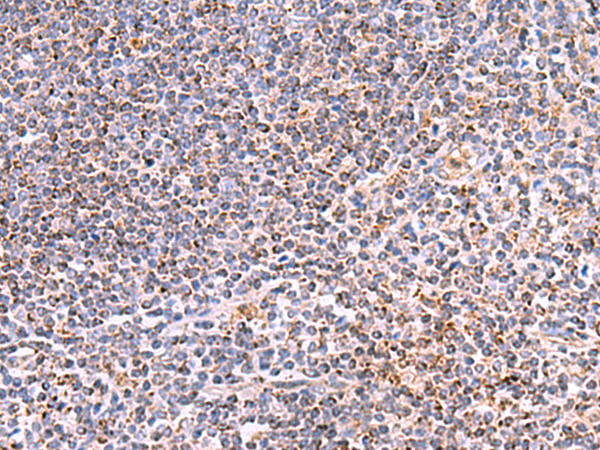

分类: 科研抗体货号: P13552别名:应用: IHC反应种属: Human